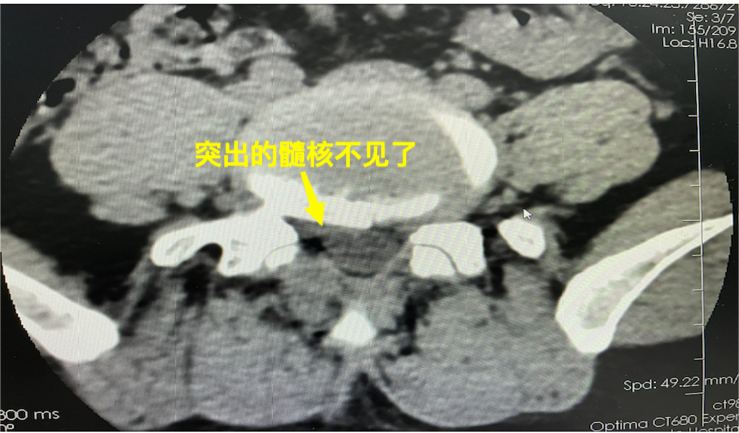

术前术后CT对比可见突出椎间盘已被成功摘除

术后复查mr见突出的椎间盘消失